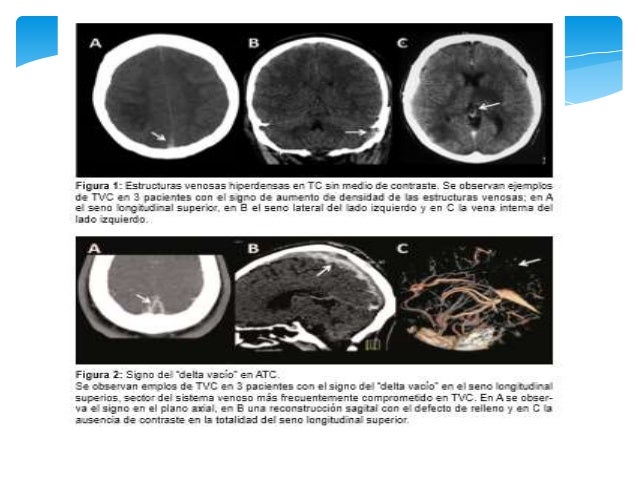

19. 19. SIGNO DEL DELTA (a) Recanalización del trombo dentro del seno, (b) Organización del coágulo, (c) Alteración de la barrera hematoencefálica , (d) Dilatación de colaterales venosas durales y peridurales. Signos del seno hiperdenso y de la cuerda: En imágenes por RM sin contraste, los vasos son habitualmente hipointensos en todas las secuencias debido a su flujo; ésto se denomina vacío de señal por flujo o también llamado “vacío de flujo”. Revista Chilena de Radiología. Vol. 16 Nº 4, año 2010; 175-187. TROMBOSIS VENOSA INTRACRANEAL

20. 20. Revista Chilena de Radiología. Vol. 16 Nº 4, año 2010; 175-187. TROMBOSIS VENOSA INTRACRANEAL

21. 21. Revista Chilena de Radiología. Vol. 16 Nº 4, año 2010; 175-187. TROMBOSIS VENOSA INTRACRANEAL